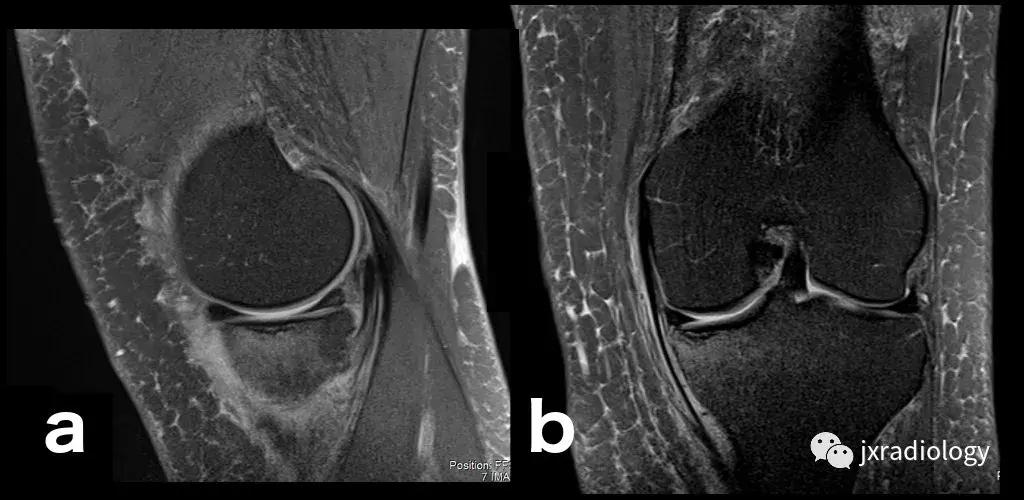

图4:SIF(软骨下不全性骨折):在过去,每当在股骨内侧髁上观察到这种软骨下病变时,它就被标记为膝关节自发性骨坏死(SONK)。 现在它被认为是一个不全性骨折。这些不全性骨折通常发生在股骨内侧髁和股骨头,并存在于老年人中(它们与骨质疏松症和生物力学改变相关,如在不稳定的半月板损伤中。 与其他应力性骨折类似,低信号的骨折线在水敏性序列(a,b:冠状和矢状PDWI-FS)上被高信号的骨髓水肿包围。

图5:长期的SIF(软骨下不全性骨折)伴股骨外侧髁软骨下塌陷、大面积水肿(不如上图中显示的内侧髁位置常见)。

图6:内侧胫骨平台上不常见的SIF(软骨下不全性骨折)(a,b:矢状和冠状PDWI-FS)。